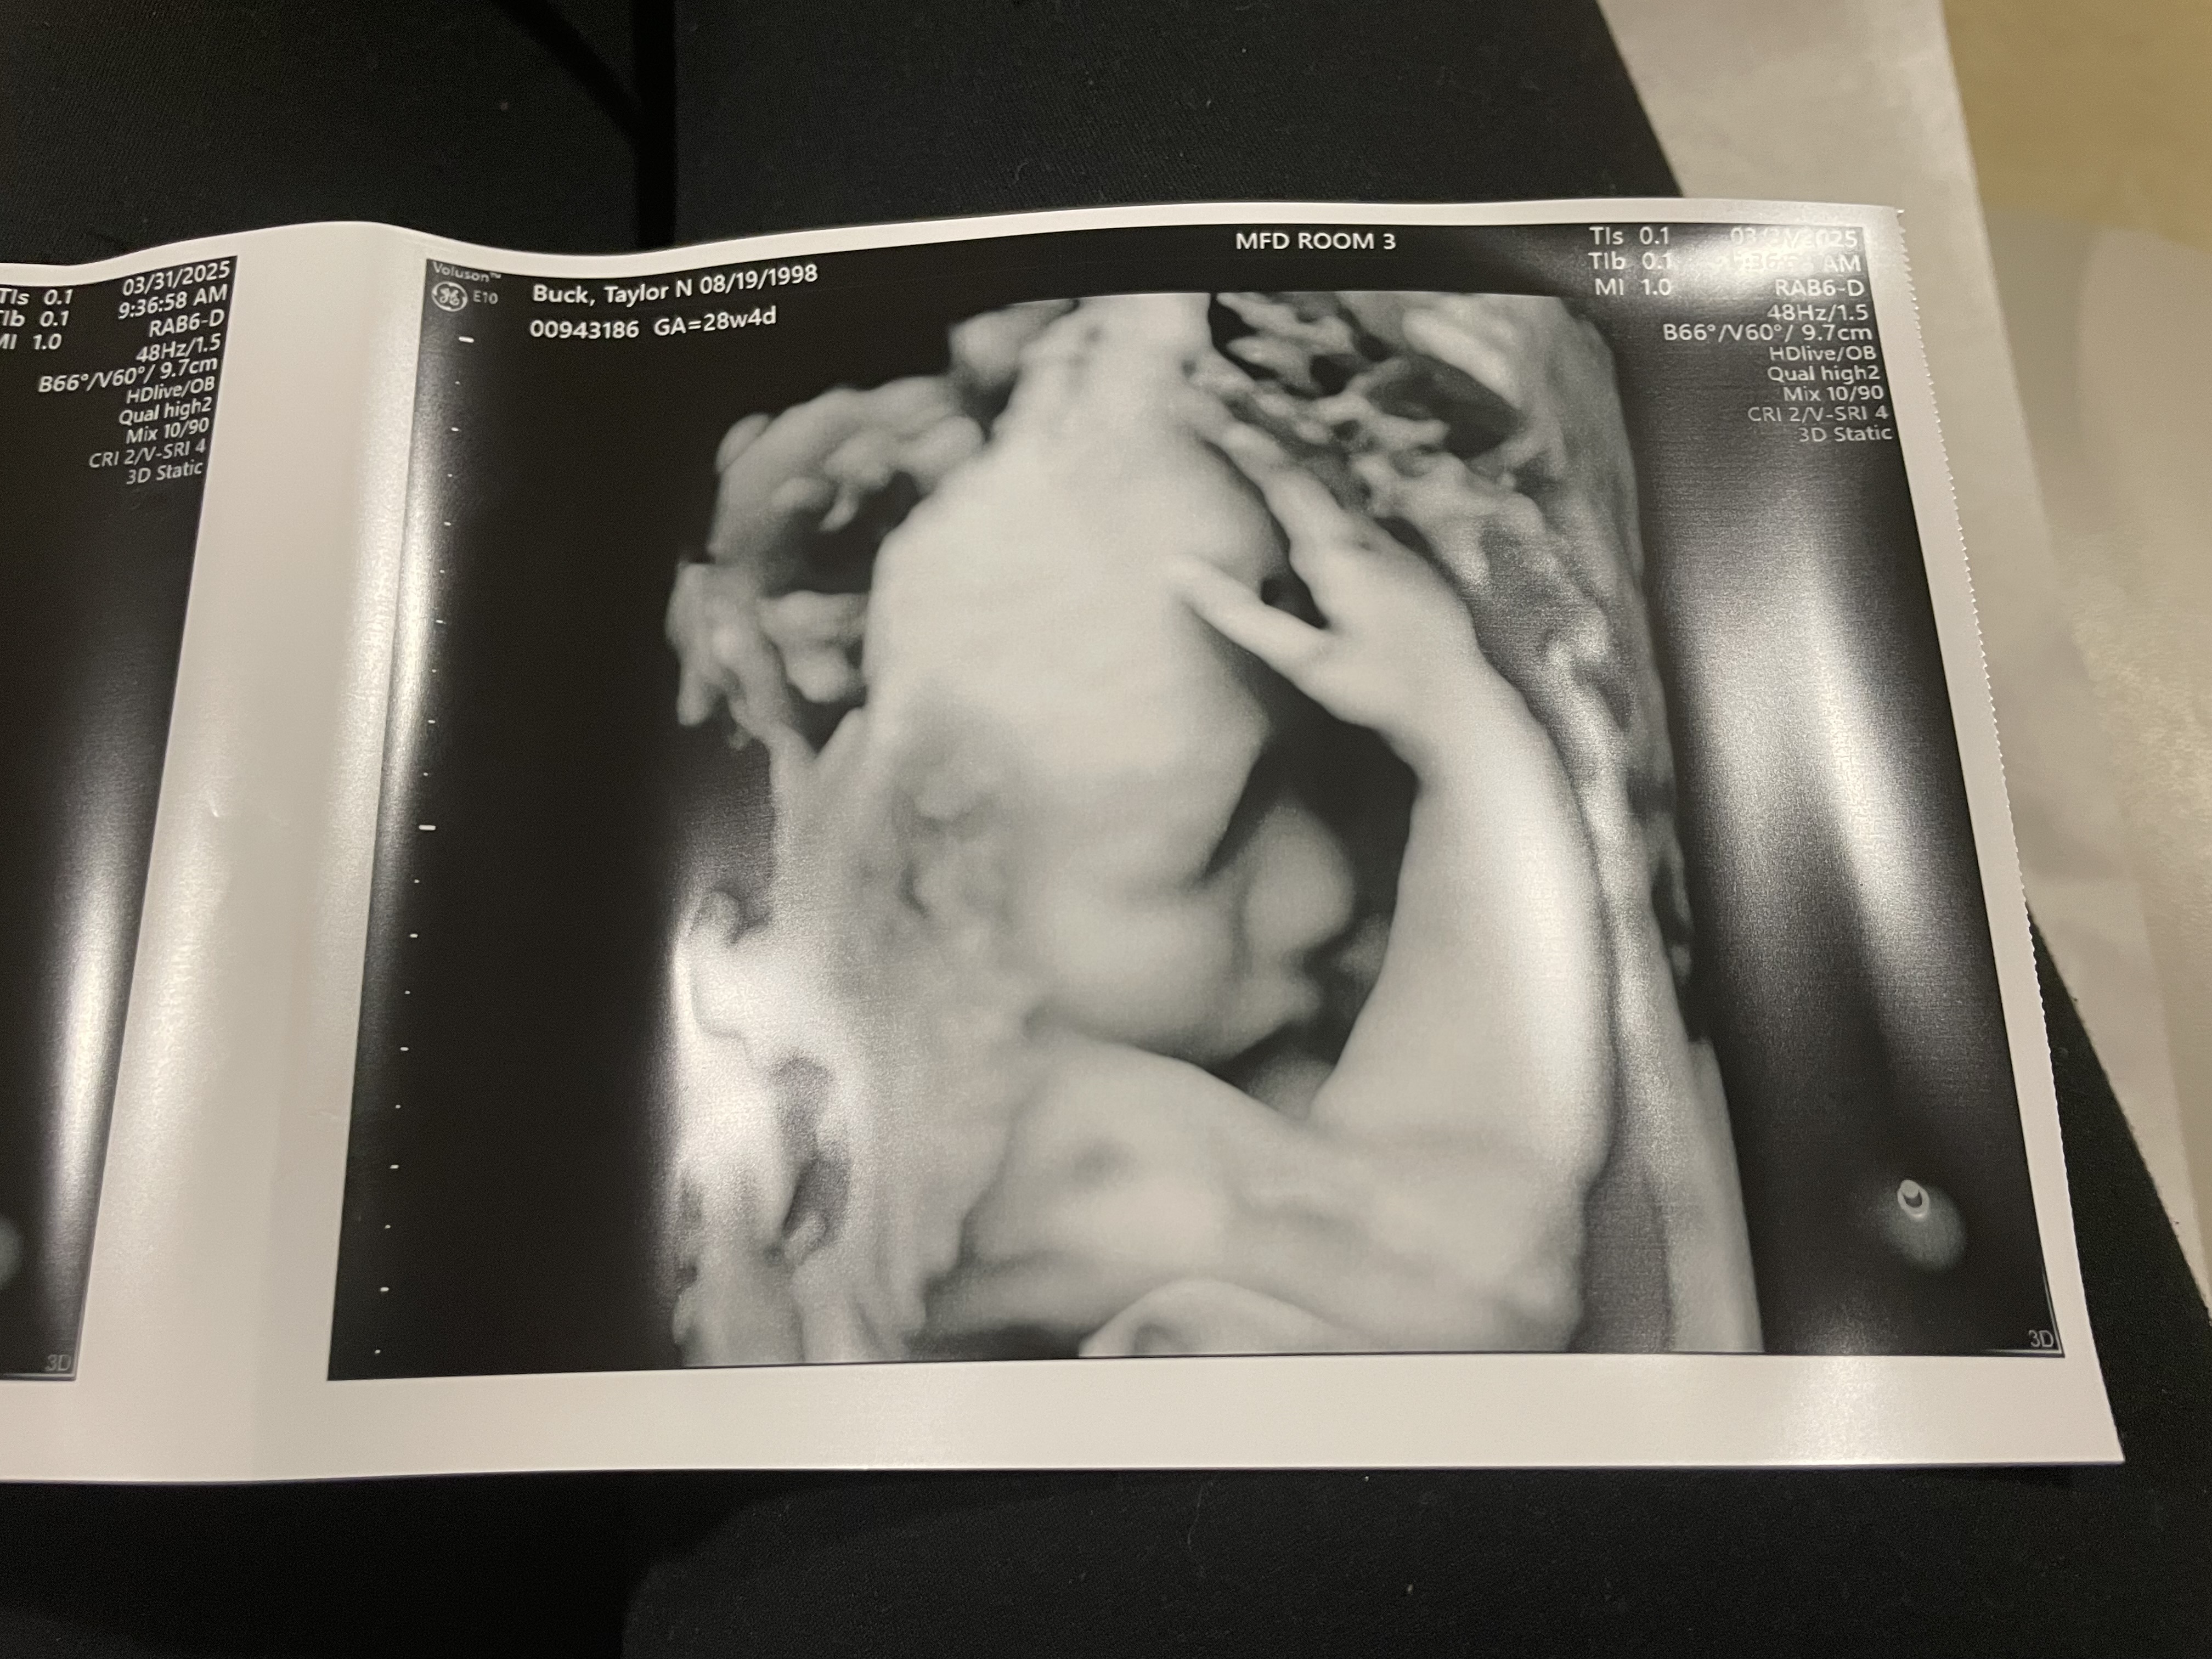

I hate that I even have to make a post like this but a couple weeks ago Jawaun and I found out our babygirl has a rare congenital heart defect called Taussig Bing but it’s a little worse than what you’ll find on google about the condition itself.. because of this rare occurrence her aorta is way smaller than they thought it would be she wont be able to pump any blood through her body so when she is born she will have to have immediate heart surgery and if they can’t do that then it’s straight to the heart transplant list she will be hooked to machines for a while unless they are able to do a successful surgery we will have to deliver her in Chicago at Luries and they will do everything possible to give our babygirl the best chances to live and im trying to cope the best I can but on top of all this news we are now worried about our financial stability being that we will have to travel to Chicago a few times before she is born and stay there a while after she’s born we wanted to start a go fund me just to maybe help out a little to keep our home maintained while we’re gone because we will both have to miss work and neither of our jobs have paid leave i don’t like to ask for help but I believe we will need as much help as we can get when the time comes there are programs we can get into after she is born to help us out but in the meantime I just wanted to try the plan is to induce me when the time comes so I can already be in Chicago and they can take her straight into surgery but on the off chance I have her early they will have to life flight her to Chicago it’s just a lot that I’m not prepared for and I don’t really know how to get prepared for it all funds will go toward gas and home expenses until assistance is available to us